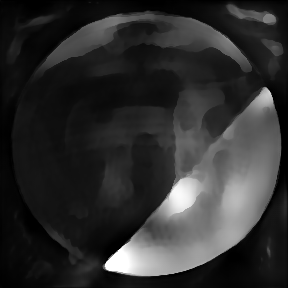

3.4.2 Data

We use here representative image data obtained using an adaptive optics (AO) supported spectral domain OCT system (citep \@BBN(Brunner et al., 2021)). Cross-sectional images (B-scans) were retrieved from two AO-OCT volumes recorded in a young healthy volunteer (27 years, female, right eye) with a field of view of approximately 4×4superscript4superscript44^{\circ}\times 4^{\circ} (corresponding to  1.4×1.4mm1.41.4𝑚𝑚1.4\times 1.4mm on the retina). Different imaging locations and focus settings were considered. One data set was recorded in the fovea with the focus of the imaging beam set to the posterior retina and one data set close to the optic disc with the focus shifted to the anterior retina. An algorithm including dispersion compensation and geometrical corrections was employed (citep \@BBN(Shirazi et al., 2020)) for the reconstruction. The images are shown on a linear intensity grey scale. The reference images, (a) in Figure 9 and 10, were obtained by manually optimizing over the parameters that define the compensation of dispersion, rotation and curvature, respectively. The examples in Figure 9 and 10 compare the chosen reference to three sub-optimal reconstructions, where (b) had a bad choice for the rotation correction parameter, (c) for the curvature correction parameter and (d) for the dispersion compensation parameter.

Refer to caption

(b) (26.88, 0.71, 0.05)

(c) (26.84, 0.72, 0.04)

(d) (29.94, 0.77, 0.06)

Figure 9: OCT reference reconstruction (a) and reconstructions with sub-optimal parameters (b)-(d) leading to geometric deviations (b)-(c) and low resolution (d). Here, (d) is wrongly judged as best reconstruction by SSIM and PSNR, LPIPS is able to ignore the small spatial deviations.

FR-IQA mismatches

Good dispersion compensation should provide images with a depth resolution that is optimized for the system at hand. In the ophthalmic application of AO-OCT, this high axial resolution allows for the visualization and identification of the different retinal layers (citep \@BBN(Shirazi et al., 2020; Brunner et al., 2021; Wojtkowski et al., 2004)), different retinal layers and structures, such as blood vessels. In the first example Figure 9 the clear separation of the different layers in the posterior retina, such as the photoreceptor bands and the retinal pigment epithelium, is crucial for clinicians/researchers who investigate the structure and function of the healthy and the diseased human retina (citep \@BBN(Jonnal et al., 2014)). Therefore, in this example, the reconstruction shown in Figure 2 (d) should have clearly been rated the lowest as the axial resolution is the lowest because of faulty dispersion compensation, which cannot be fixed by further post-processing. In the second example Figure 10, a cross-sectional view of three retinal vessels which are embedded in the nerve fibre layer is given. Changes in the thickness of vessel walls are an important early biomarker for retinal diseases such as diabetic retinopathy, cf. (citep \@BBN(Bakker et al., 2022)). Again, the reconstruction with faulty dispersion compensation shown in Figure 10(d) should have been rated the lowest. The loss in axial resolution worsens the visualisation of the vessel walls and would lead to inaccurate measurements of the vessel wall thickness. In the current version of the algorithm the parameters which determine the amount of dispersion, rotation and curvature compensation applied by the reconstruction algorithm have to be set manually. Therefore, automated evaluation would be very helpful to fasten the process. The standard metrics are not suitable here, as PSNR and SSIM wrongly assess that reconstruction as the best, and, as expected, penalize harder the geometric deviations in (b) and (c). The geometric deviations are not beneficial, but could be fixed by post-processing unlike image (d).